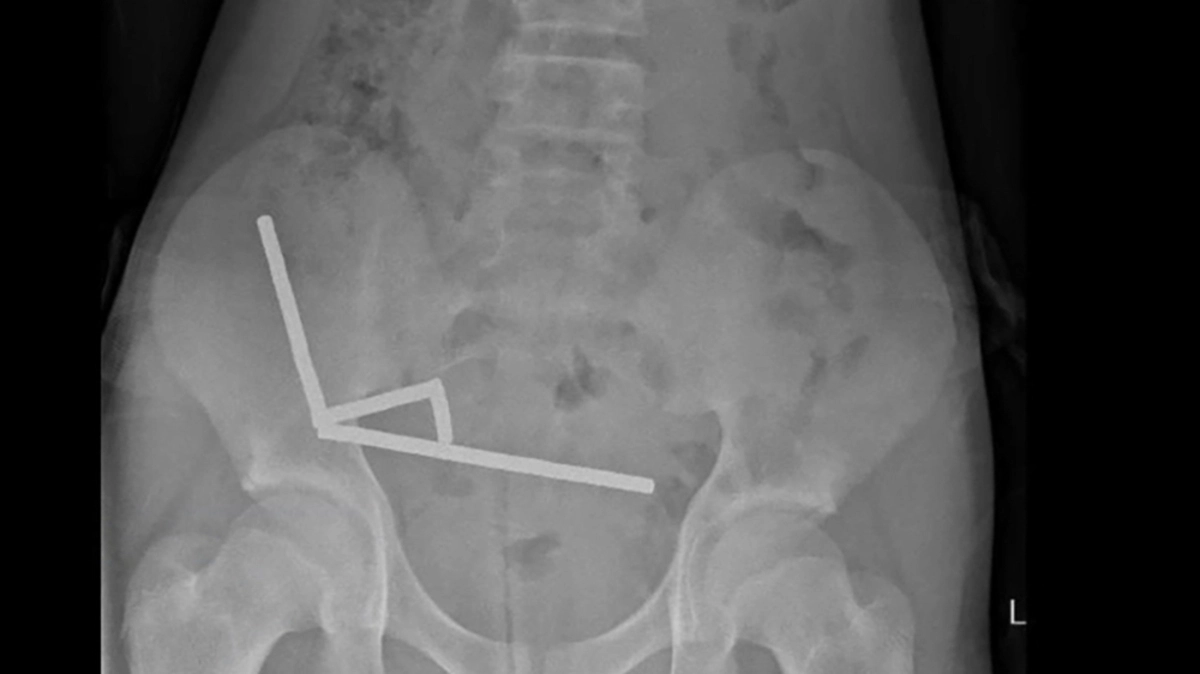

Chirurgen in Neuseeland haben dutzende Magneten aus den Gedärmen eines 13 Jahre alten Buben entfernt. Der Bub habe bis zu 100 Hochleistungsmagneten heruntergeschluckt, die er zuvor beim Billig-Onlinehändler Temu bestellt hatte, teilten die Ärzte am Freitag mit. Der 13-Jährige habe vier Tage lang unter Unterleibsschmerzen gelitten, bevor er in das Tauranga-Krankenhaus auf der Nordinsel Neuseelands eingeliefert worden sei.

Die Magneten ordneten sich im Darm neu an | Die Magneten ordneten sich im Darm neu an

Die Magneten ordneten sich im Darm neu an